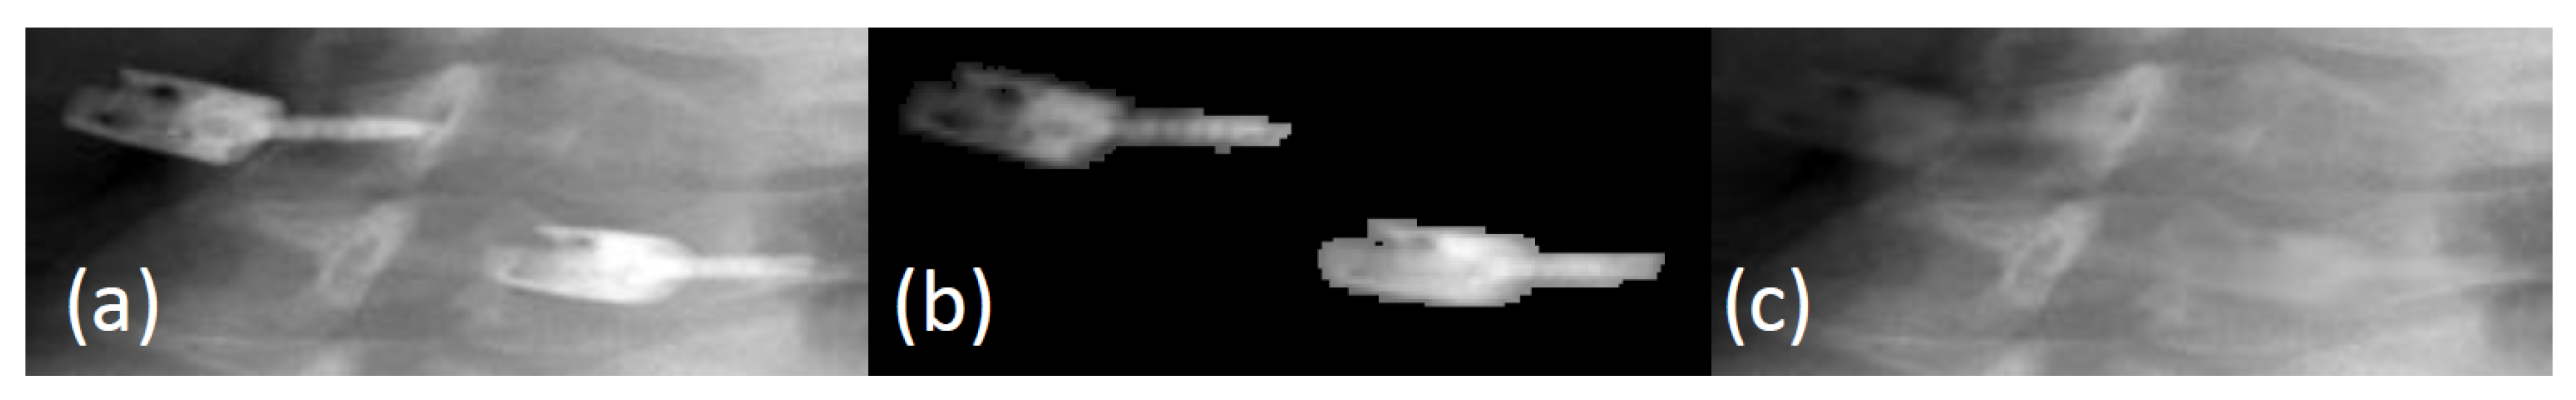

Before we can correct the ray profiles (see Section 2.3), we need to know whether a sample point in a given ray profile originates from metal (or not). For this purpose, we segment the screws from the uncorrected CT volume in the following two steps. In the first step, we use a simple threshold-based segmentation approach to get coarsely metal-only segmented result. After that, we apply the DBSCAN (Density-based spatial clustering of applications with noise) algorithm [33] to the segmented structures. DBSCAN is a popular clustering algorithm which classifies points that are not well connected to a cluster as outliers. We found that DBSCAN did very well to remove any remaining noise and obtain an accurate segmentation of the metal objects (in our case, the screws). The clean segmentation also allows us to precisely determine how many screws were implanted. Optionally, we might also include prior geometric knowledge to accelerate the process and to further improve the clustering accuracy. Figure 4 shows a screw extracted from an uncorrected CT volume. Figure 4c is what we refer to as the metal-only CT volume.

Figure 4. Metal localization: (a) uncorrected CT volume; (b) extracted high density materials using the BHT; and (c) final results with DBSCAN.